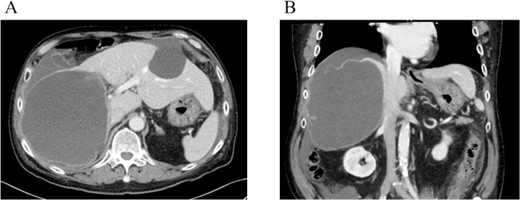

On referral to our hospital, his vital signs were within normal limits. The abdominal examination revealed rebound tenderness in his right upper quadrant region. There was no abdominal distension. The initial laboratory tests demonstrated a normal hemoglobin (10.2 g/dl) and elevated C-reactive protein levels (9.6 mg/dl). The results of serum tumor markers were as the follows: CA19-9, 193 784.3 U/ml; carbohydrate antigen 125 (CA125), 91.6 U/ml; carcinoembryonic antigen (CEA), 2.1 ng/ml; α-fetoprotein (AFP), 3.0 ng/ml; des-γ-carboxy prothrombin (DCP), 19 mAU/ml (Table 1). Dynamic CT showed a large cystic lesion (17 cm × 14 cm × 12 cm) in the right liver and discontinuation of the cystic wall and retention of ascites mainly the right subphrenic region (Fig. 1). T2-weighted single shot turbo spin echo magnetic resonance imaging (MRI) showed a-low intensity region with dorsal predominance in the high-intensity area and fluid–fluid level (Fig. 2). Gadoxetic acid (Gd-EOB) enhanced MRI didn’t show any lesion suggesting mural nodule in the cystic wall in any phase (Fig. 3). Paracentesis showed bloody fluid and the tumor marker levels in the sampled ascites were as the follows: CA19-9, 2 672 400.0 U/ml; CA125, 2618.9 U/ml; CEA, 41.7 ng/ml; AFP, 1.4 ng/ml; and DCP, 10 mAU/ml (Table 1). Cytology of the ascites showed no findings of malignancy.

T2-weighted single shot turbo spin echo MRI showed a low intensity region with dorsal predominance in the high-intensity area, and fluid–fluid level.